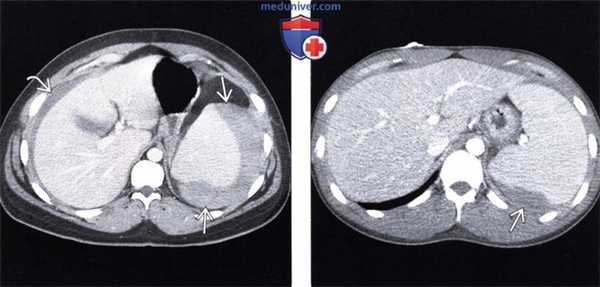

(Слева) Аксиальная КТ с контрастом у пациента с мононуклеозом: визуализируется свернувшаяся кровь вокруг увеличенной селезенки («сторожевой» сгусток) и внутрибрюшное кровоизлияние низкой плотности (гиподенсное). В данном случае спонтанный разрыв селезенки не потребовал оперативного вмешательства.

(Справа) При аксиальной КТ с контрастным усилением у пациента с мононуклеозом была выявлена гематома по краю селезенки, возникшая в результате ее разрыва. В этом случае пациенту также не потребовалось оперативное лечение. (Слева) При аксиальной КТ без контрастного усиления выявлена увеличенная селезенка с прилежащей к краю органа гиперденсной гематомой («сторожевой» сгусток) и свободная гиподенсная кровь в брюшной полости.

(Справа) При аксиальной КТ с контрастным усилением у пациента с мононуклеозом была выявлена гематома по краю селезенки, возникшая в результате ее разрыва. В этом случае пациенту также не потребовалось оперативное лечение.

3. КТ изменения брюшной полости при мононуклеозе:

• Селезенка:

о Спленомегалия

- Частая находка (60% пациентов), даже если селезенка не пальпируется при физикальном обследовании

о Разрыв селезенки

- Периспленальная и подкапсульная гематома («сторожевой» сгусток крови при КТ)

- Увеличенная селезенка с гиподенсными участками при КТ